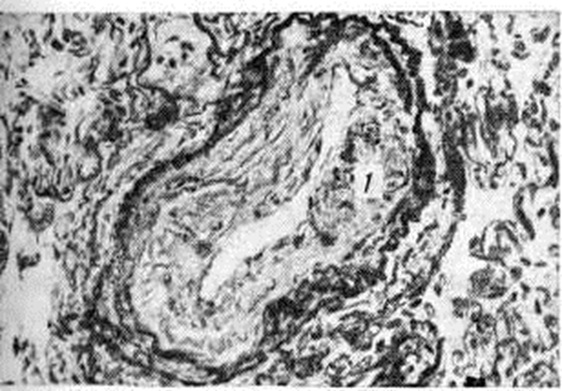

Рис. 1.

Микропрепарат мелкой ветви лёгочной артерии в норме (для сравнения): 1— стенка сосуда; 2— просвет сосуда.

Прекапиллярная форма наиболее часто развивается на фоне хронический болезней лёгких, сопровождающихся эмфиземой со склерозом альвеолярных перегородок. Возникающее при этом сопротивление кровотоку в капиллярах приводит к переполнению кровью мелких артерий, вследствие чего просвет их растягивается, циркулярный мышечный слой истончается и вместе с тем за пределами внутренней эластической мембраны формируется более или менее массивный продольный мышечный слой (рисунок 1 и 2). В венозном русле отмечается атрофия мышечных элементов, просвет вен спадается, внутренняя оболочка склерозируется.